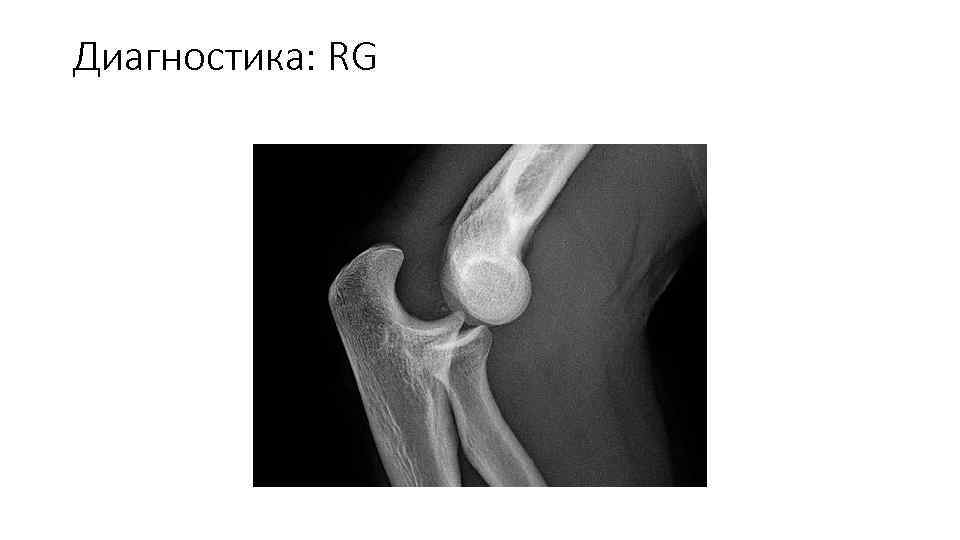

Диагностика: RG